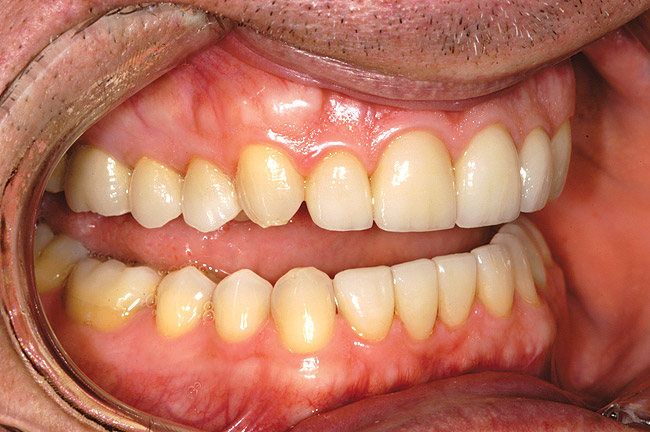

Figure 7a  Teeth Nos. 4, 5, and 30 were in need of indirect restorations and were treatment planned for all-porcelain, adhesively retained restorations.

Figure 7a

Figure 7c  Harmonious blending of indirect restorations and natural tooth structure provides improved esthetics and conservation of tooth structure.

Figure 7c

Figure 7d  Note that the facial margin was carried to the free gingival margin on the maxillary bicuspids. However, in areas of less esthetic significance, such as the tooth No. 30, the margin was kept supragingival in an effort to further conserve tooth structure.

Figure 7d